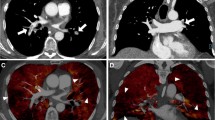

Figure 2 exemplifies the semiautomatically derived normal and malperfused lung areas in a control, a patient with acute PE, and a patient with CTEPH. Patients with acute PE had a significantly lower ID in the MPA as compared to controls (p = 0.046). Right-to-left-heart contrast transit via the pulmonary vascular bed, as indicated by the ID in the LA, revealed no differences between groups based on post hoc analysis. Malperfused lung areas in acute PE and CTEPH were perfused less when being standardized to the MPA (IDmean,MPA) and more homogenous (IDskewness) in comparison to controls (IDmean,MPA: acute PE, 0.022 ± 0.005; CTEPH, 0.023 ± 0.004; controls, 0.028 ± 0.005; IDskewness: acute PE, 0.03 ± 0.48; CTEPH, −0.06 ± 0.38; controls, −0.57 ± 0.45; p for all < 0.001; Table 2 and Fig. 3).

Conventional reconstructions (A1–A6), corresponding IDO images (B1–B6), and automatically derived normal (C1–C6) and malperfused lung areas (D1–D6) illustrating the physiological ventro-dorsal gradient of pulmonary blood volume in the supine patient as well as the visually similar perfusion patterns in acute PE (middle) and CTEPH (bottom). IDO, iodine density overlay; APE, acute pulmonary embolism; CTEPH, chronic thromboembolic pulmonary hypertension

Differentiation between acute PE and CTEPH

In acute PE, normal perfused lung areas took up more iodine on average than in CTEPH when being normalized to the MPA (IDmean,MPA: 0.13 ± 0.04 vs. 0.10 ± 0.02, p < 0.001). Normalizing mean iodine uptake in perfusion defects to the LA patients with acute PE showed a reduced perfusion compared to CTEPH patients and controls (IDmean,LA, both p < 0.001; Figs. 4 and Fig. 5).

dlDECT-based assessment of pulmonary perfusion via systemic collaterals in a patient with acute PE (top) and a patient suffering from CTEPH (bottom). Axial and paracoronar multiplanar reconstructions show the enlarged bronchial arteries (>1.5 mm) in the CTEPH patient (B3 and B4) leading to an increased perfusion in embolic lung areas as indicated by an increased IDmean,LA (C1/2 vs. C3/4). APE, acute pulmonary embolism; CTEPH, chronic thromboembolic pulmonary hypertension; ID, iodine density; LA, left atrium